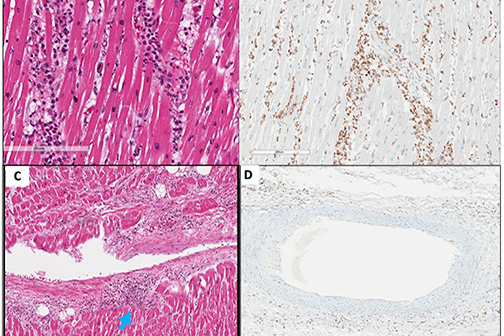

LSU Health New Orleans Researchers Discover a Key Failure in AMD that May Lead to Progression & Vision Loss

Research led by Nicolas Bazan, MD, PhD, Boyd Professor, Ernest C. and Yvette C. Villere Chair for the Study of Retinal Degeneration, and Director of the Neuroscience Center of Excellence at LSU Health New Orleans School of Medicine, suggests that age-related macular degeneration (AMD) decreases an essential fatty acid, preventing the formation of a class of protective molecules and reducing repair potential. The discovery may also open new therapeutic avenues for AMD. More

LSU Health Contributes to Research Suggesting Late-Onset Retinal Degeneration Mechanism & Potential Rx

A study led by the National Eye Institute (NEI) that included five researchers from the Bazan Lab at the LSU Health New Orleans Neuroscience Center of Excellence has discovered how late-onset retinal degeneration can develop and a surprising potential therapeutic -- metformin. The results are published online in Communications Biology, a Nature journal. More